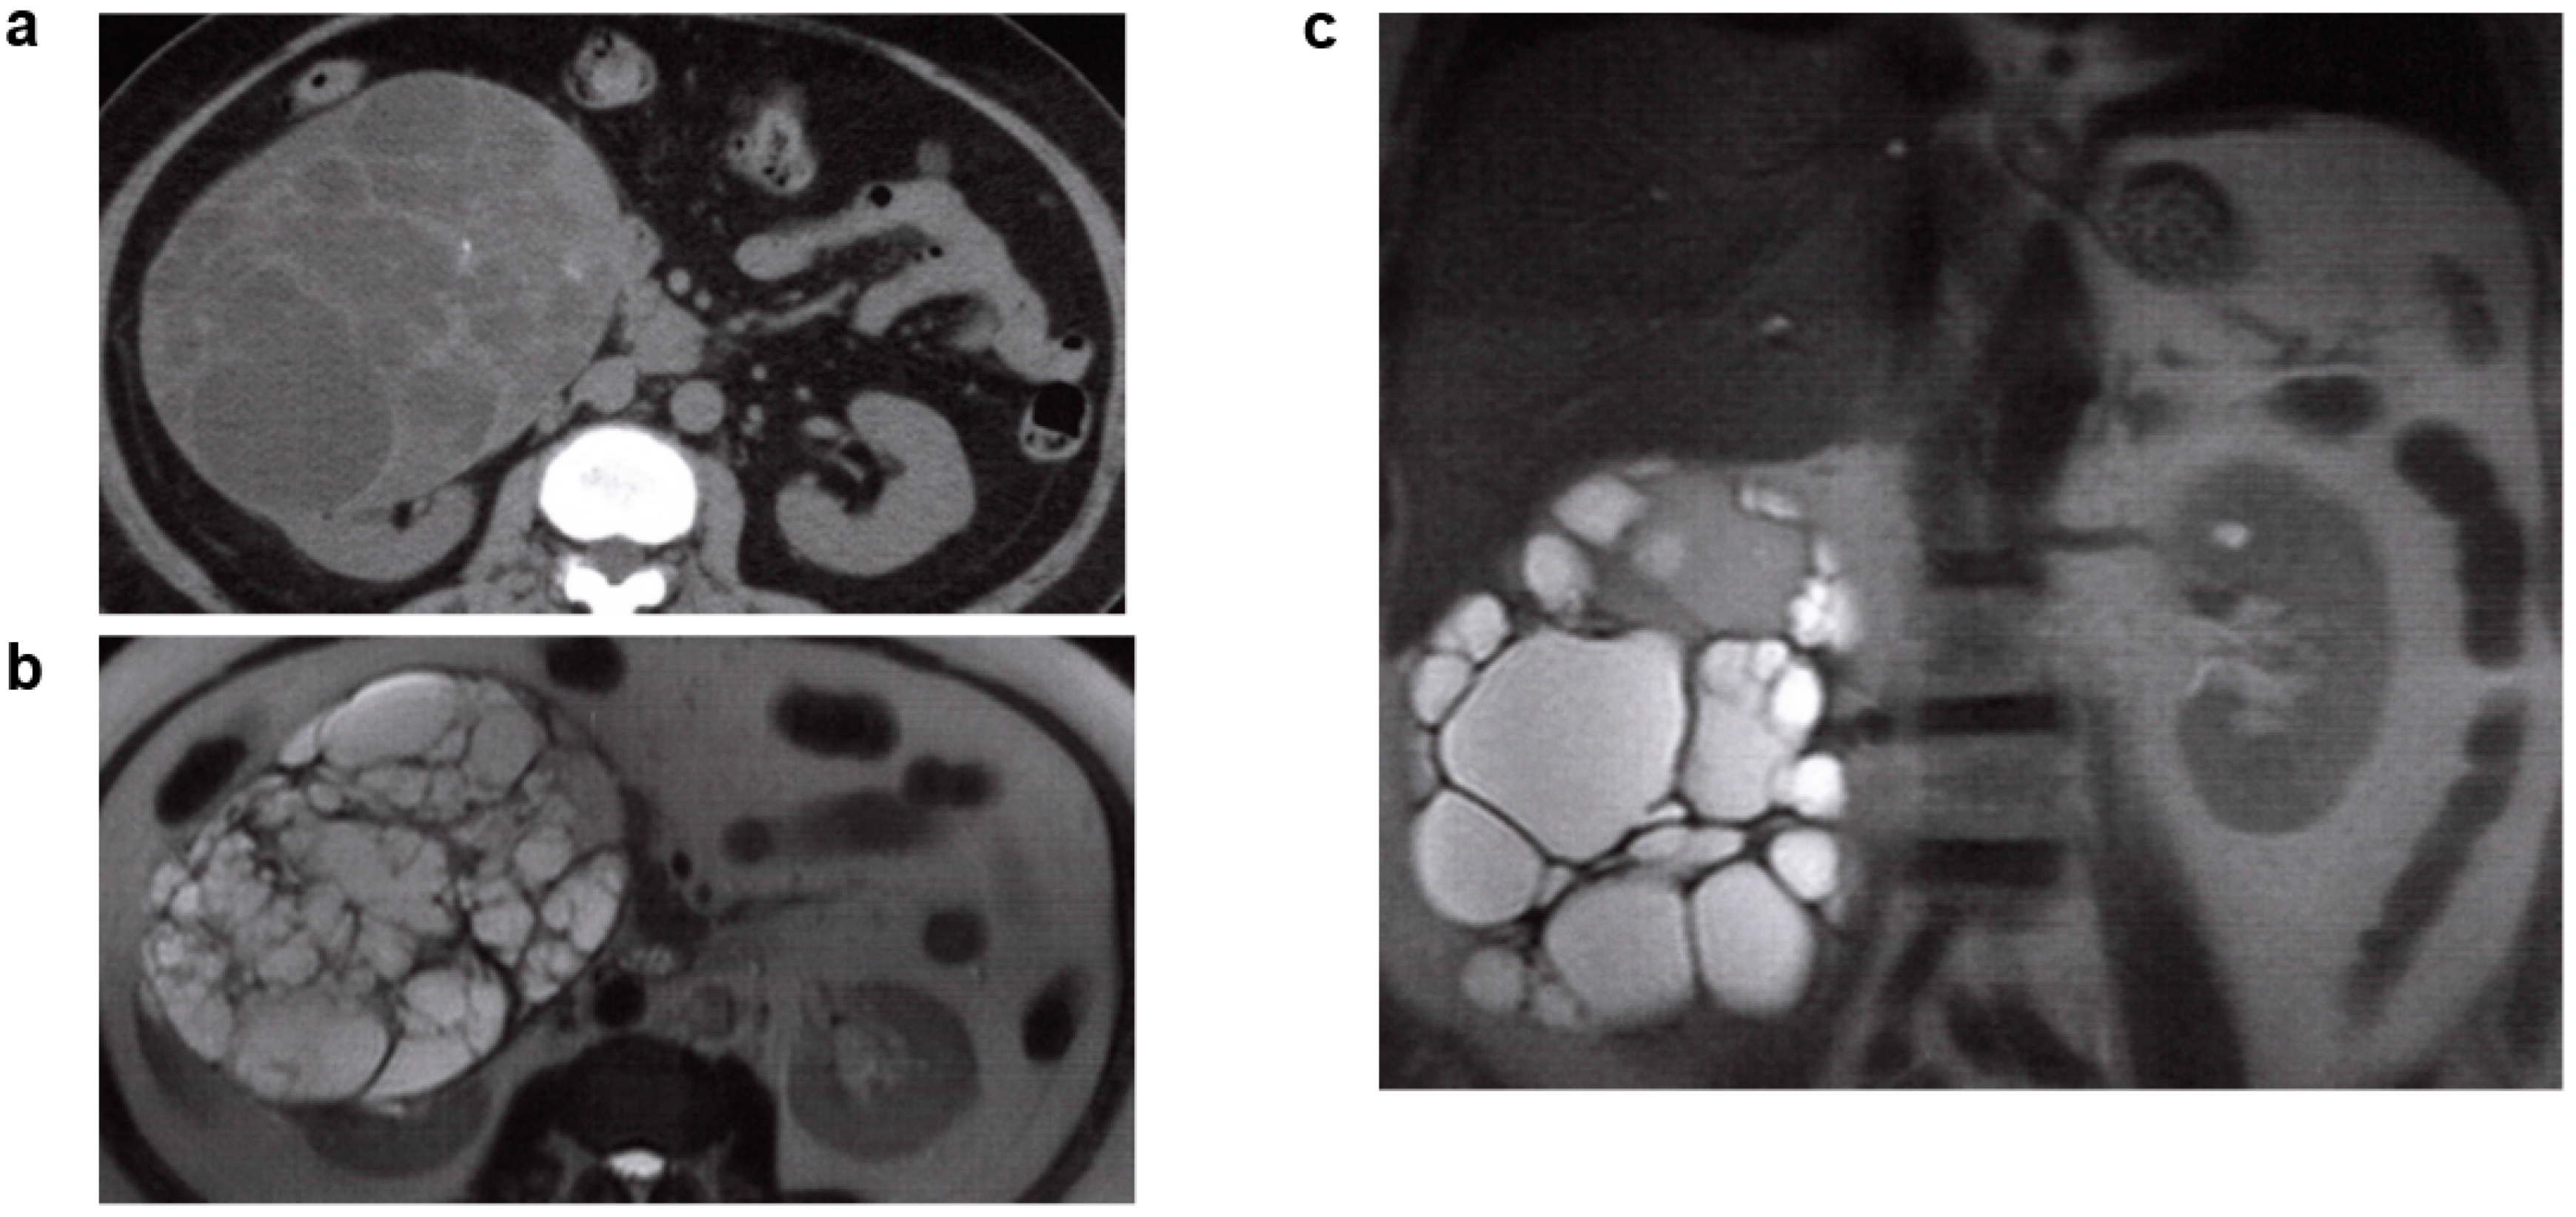

2.3. Multilocular Renal Cyst (Also Referred to as Multilocular Cystic Nephroma or Polycystic Nephroma)

2.4. Multicystic Kidney/Multicystic Dysplastic Kidney (MCDK)

2.5. Unilateral Renal Cystic Disease (URCD)